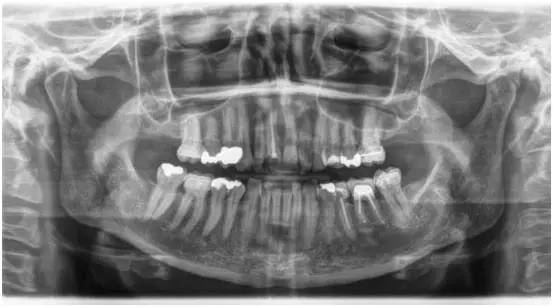

牙合翼片示意图,咬合翼片的图片

每年一次咬合翼片,检查后牙邻面早期龋齿.牙就没坏过,那就两年一次.

咬合翼片的图片

咬合翼片什么样子

咬合翼片

口腔咬合翼片图片

牙合翼片的正常图像